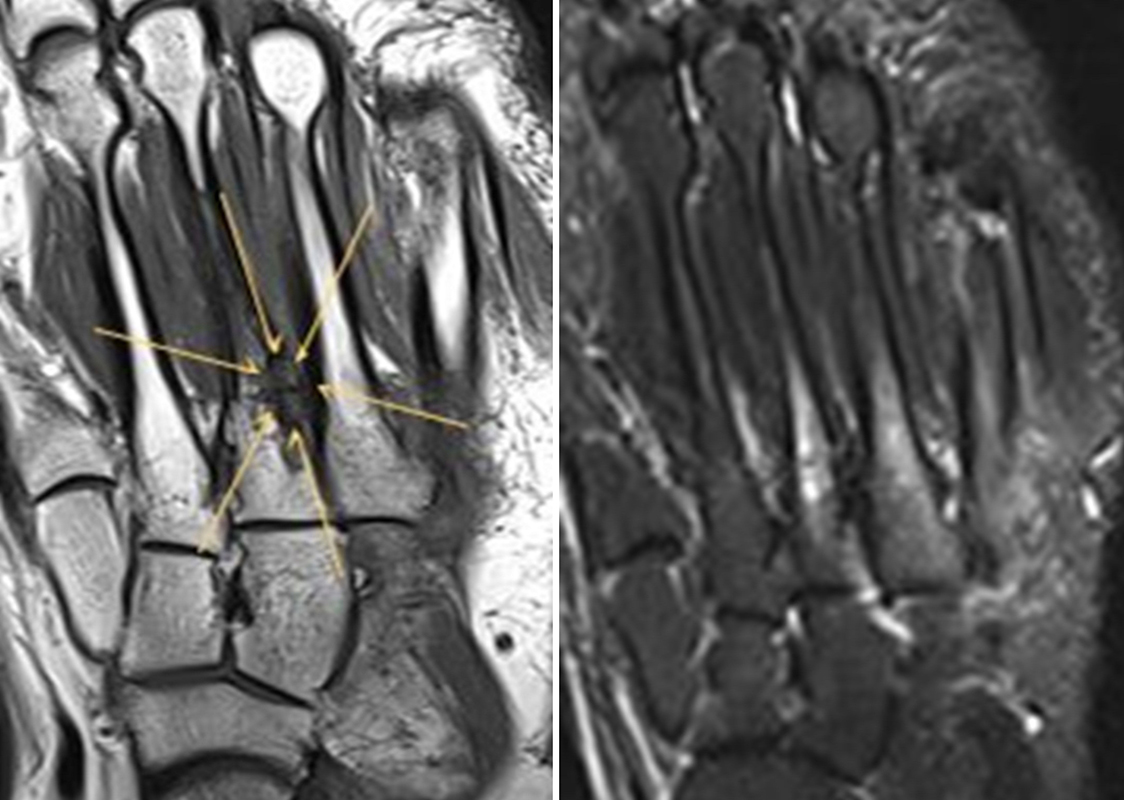

Abbildung 3.3.a und b: Patient mit rezidivierenden Schmerzen, zeitweise auch Schwellung und Überwärmung im linken Vorfuß (medialseitig auf Höhe der Fußwurzel/Mittelfußknochen) seit einem Umknicktrauma vor 4 Jahren. Nativradiologisch unauffällig. Das MRT zeigte eine Ruptur des Ligamentum fibulotalare anterius sowie einen knöchernen Ausriss aus der distalen Fibula; zusätzlich Verdacht auf Sinus tarsi Syndrom bei einem Ganglion medial am unteren Sprunggelenk. Die SPECT/CT zeigte eine Stressreaktion am Ansatz der Tibialis-posterior-Sehne des linken Fußes bei einem Os naviculare Typ III, was mit dem klinischen Befund korrelierte. Das MRT wies in diesem Bereich keine wegweisenden Signalveränderungen auf (Abbildung 3.3.a); im SPECT/CT eindeutig erhöhter Metabolismus ohne weitere Auffälligkeiten (Abbildung 3.3.b).